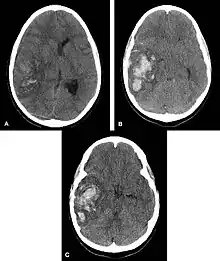

Multiple intraparenchymal hemorrhage

Intraparenchymal hemorrhage (IPH) is one form of intracerebral bleeding in which there is bleeding within brain parenchyma. The other form is intraventricular hemorrhage (IVH).[1]

Hemorrhagic neoplasms are more complex, heterogeneous bleeds often with associated edema. These hemorrhages are related to tumor necrosis, vascular invasion and neovascularity. Glioblastomas are the most common primary malignancies to hemorrhage while thyroid, renal cell carcinoma, melanoma, and lung cancer are the most common causes of hemorrhage from metastatic disease.

Nontraumatic intraparenchymal hemorrhage most commonly results from hypertensive damage to blood vessel walls e.g.: - hypertension - eclampsia - drug abuse, but it also may be due to autoregulatory dysfunction with excessive cerebral blood flow e.g.: - reperfusion injury - hemorrhagic transformation - cold exposure - rupture of an aneurysm or arteriovenous malformation (AVM) - arteriopathy (e.g. cerebral amyloid angiopathy, moyamoya) - altered hemostasis (e.g. thrombolysis, anticoagulation, bleeding diathesis) - hemorrhagic necrosis (e.g. tumor, infection) - venous outflow obstruction (e.g. cerebral venous sinus thrombosis). Nonpenetrating and penetrating cranial trauma can also be common causes of intracerebral hemorrhage.